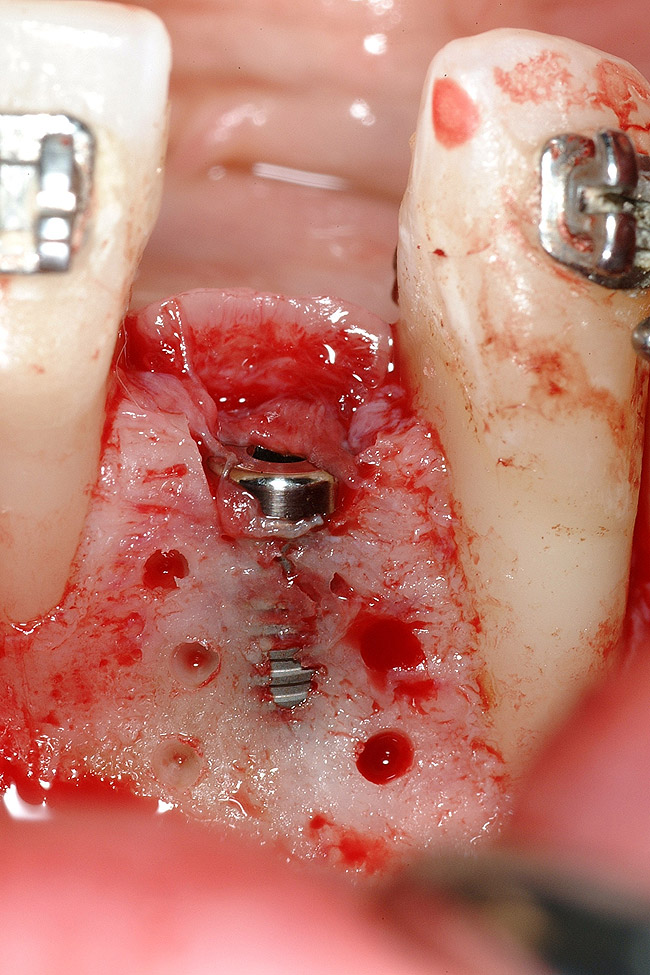

Figure 4  Vertical ridge defect in site No. 22.

Figure 4

Figure 5  Horizontal ridge defect in site No. 22.

Figure 5

The patient had no medical concerns and had a history of an implant placement in December 2002 when she was 25 years old. In February 2005, she presented with a mobile implant and an associated advanced peri-implantitis. Radiographic review at the initial examination demonstrated significant destruction of the dentoalveolar ridge around the implant as well as around the adjacent natural dentition. Emergency-based treatment involved surgical implant removal only and debridement of the infection (Figure 4 and Figure 5). Following uneventful healing, an advanced ridge defect was apparent at the edentulous site and moderate and advanced attachment loss noted at No. 22D and No. 21M, respectively (Figure 6 and Figure 7). This case demonstrates bone loss of two separate origins: lack of bone because of tooth agenesis and destruction of bone from inflammatory peri-implantitis.

Figure 18  Implant placement with resulting facial dehiscence. Cortical perforations placed to promote angiogenesis.

Figure 18